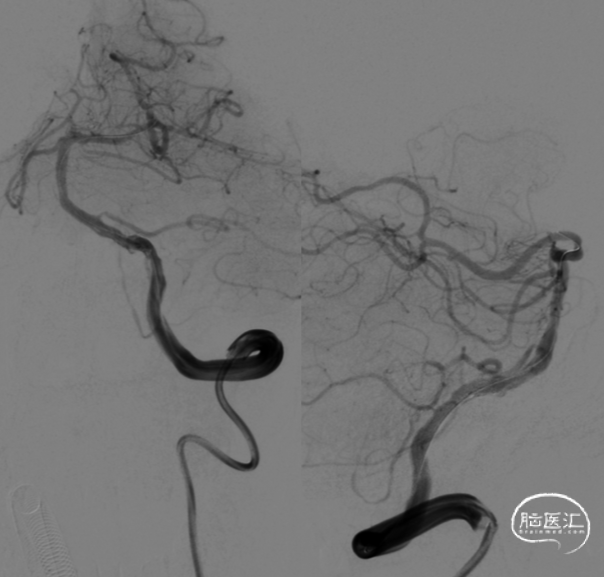

DSA(2022-01-19):

L-ICA

L-VA

R-ICA

复查DSA:左侧椎动脉V4段重度狭窄。

术前影像。

球囊扩张后狭窄有所改善。

支架顺利到达病变位置到位。

充盈球囊,释放支架。

支架释放后。